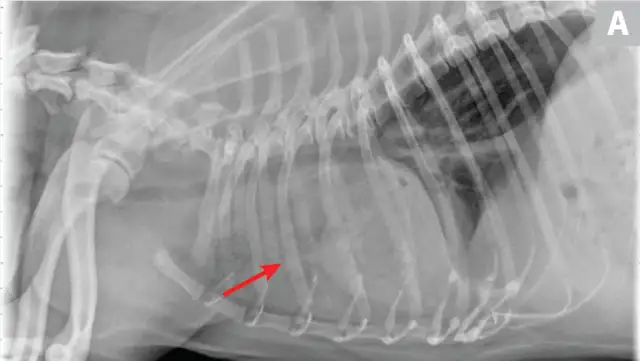

CDV should be suspected in poorly vaccinated dogs with multiorgan involvement. Dogs with CDV may have exhibited only respiratory signs before developing characteristic nonrespiratory signs.12 Radiographs may reveal a diffuse interstitial pattern (Figure 2). Diagnosis is supported by compatible clinical signs and complementary diagnostic testing (ie, real-time reverse transcription polymerase chain reaction [RT-PCR], serology, CSF pleocytosis). Conjunctival scraping and tissue-based immunohistochemistry may confirm diagnosis.

FIGURE 2

CDV pneumonia with a diffuse interstitial pattern confirmed by multisystemic signs, urine RT-PCR, and necropsy